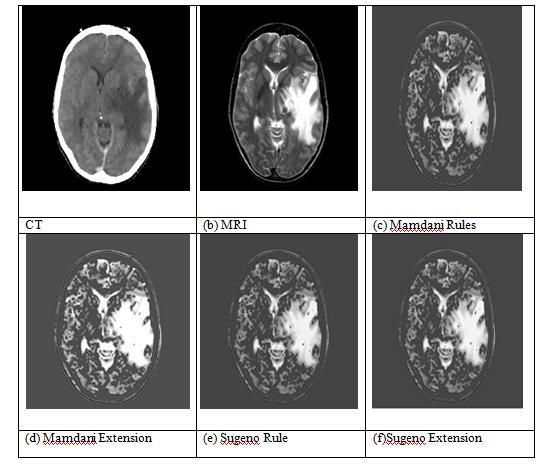

Fig-3: Fusion CT and MRI-set 1 picture

The set 1 CT and MRI image fusion findings. The CT input pictureispicture(a),whiletheMRIinputimageisImage(b). The fused pictures from the Mamdani rules are shown in Image(c), while the fused images from the Mamdani extension method are shown in Image(d). It is clear from

pictures (c) and (d) that the fused image produced by MamdanirulesisinferiortotheimagegeneratedbyMamdani extension. The fused image obtained from the Sugeno extensionmethodisImage(f),whilethefusedimageobtained fromtheSugenorulesisImage(e).Ithasbeendemonstrated bythephotos(e)and(f)thatthefusedimageproducedby theSugenoextensionissignificantlysuperiortotheoutput imageproducedbytheSugenorules.Fouroutputphotosare compared, and it is evident that the fused images from Sugeno FIS have higher quality and resolution than those fromMamdaniFIS.

Table2aboveliststheobjectivemeasuresfortheset1CT and MRI images. Here, calculations are made for entropy, mutual information, and edge-based quality metrics. The entropyvaluesforMamdaniandSugenoaresame.Incontrast toMamdaniFIS,SugenoFISimprovisesMutualInformation values.MamdaniandSugenorulesbothhavethesameEdge Based Quality Metric values, yet Mamdani has higher (QAB/F)valuesthanSugeno.